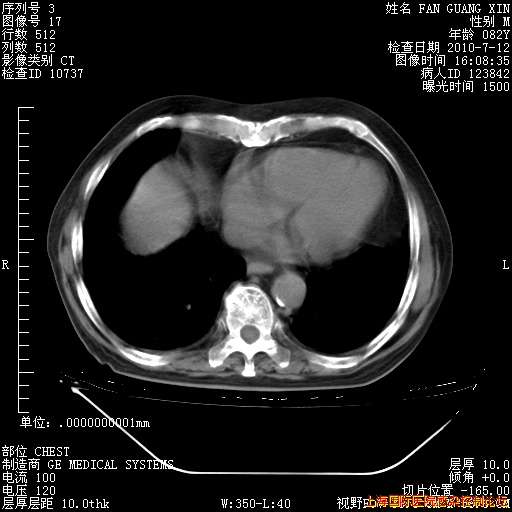

6月12日纵膈窗

6月10日改甲强龙80mg qd ,在南京年会期间体温不稳,18日有一次寒战后体温达39度。19日开始用甲强龙60mg bid ,加量后第二天就不发热。本打算在两周后即7月3日减量,但是7月2日洗澡受凉、发热、咳嗽、鼻音,口服复方大青叶片,甲强龙120mg用到9日(整整20天)。

自昨天起甲强龙改为80mg qd。

在抗结核治疗2周后一般情况逐渐好转。

整整相隔30天的肺部CT好像有所好转啊。甲强龙减量第3天,需要观察体温。